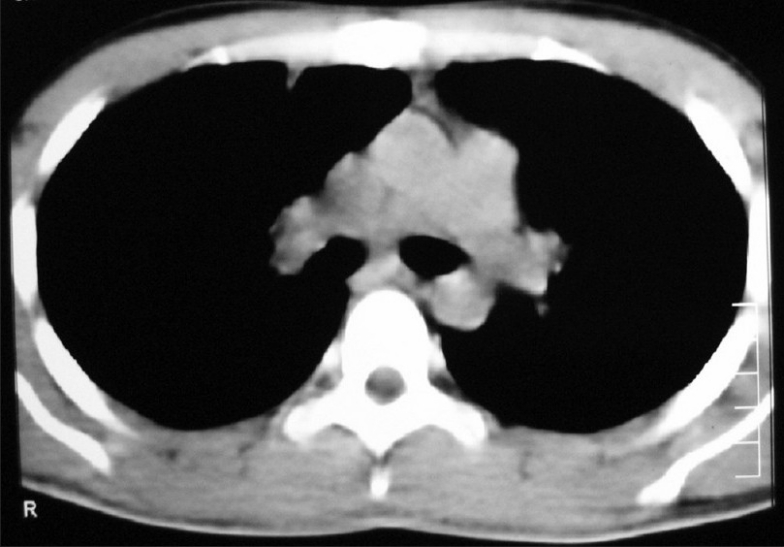

He presented in June 2007 with dull-aching retrosternal and right-sided chest pain with exertional dyspnea and dysphagia for solids. On examination, there was impaired note to percussion over the right mammary and infra-axillary regions with diminished breath sounds. A 3 ×3 cm mass was palpable over the epigastric region. Both testes were normal. Chest X-ray showed superior mediastinal widening with homogenous opacity in the right mid and lower zone [Figure 6]. CECT chest showed an anterior mediastinal mass extending into middle mediastinum with subpleural metastases to posterior segment of right lower lobe [Figure 7].

| Figure 7 CT chest (2007 ) shows recurrence of anterior mediastinal mass extenting into right side of chest

The diagnosis of recurrent seminoma of thymus with metastases to right lung, para- and peri-aortic lymph nodes was made. The patient was started on BEP (bleomycin, etoposide, cisplatin). After four courses of chemo, complete disappearance of the mediastinal mass and lung metastatic lesions and reduction of abdominal lymph nodes to sub-centimeter size were noted [Figures [Figures99–11].

| Figure 10 CT chest (2008) shows complete disappearance of the mass after chemo